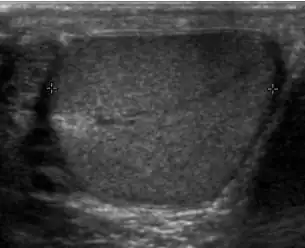

At ultrasound, the findings of acute epididymitis include an enlarged hypoechoic or hyperechoic (presumably secondary to hemorrhage) epididymis [Fig. 20a]. Other signs of inflammation such as increased vascularity, reactive hydrocele, pyocele and scrotal wall thickening may also be present. Testicular involvement is confirmed by the presence of testicular enlargement and an inhomogeneous echotexture. Hypervascularity on color Doppler images [Fig. 20b] is a well-established diagnostic criterion and may be the only imaging finding of epididymo-orchitis in some men.

-

Doppler ultrasound of epididymitis, seen as a substantial increase in blood flow in the left epididymis (top image), while it is normal in the right (bottom image). The thickness of the epididymis (between yellow crosses) is only slightly increased (7 mm). -

Doppler ultrasound of the scrotum of the same case, in the axial plane, showing orchitis (as part of epididymo-orchitis) as hypoechogenic and slightly heterogenic left testicular tissue (right in image), with an increased blood flow. There is also swelling of peritesticular tissue.